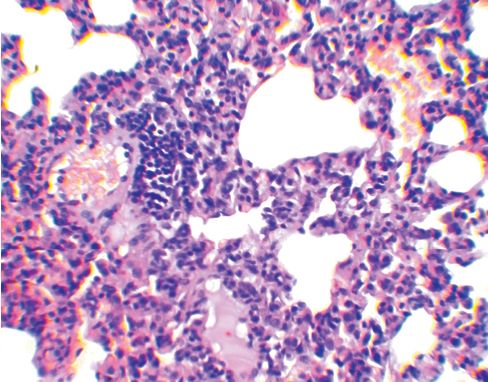

УДК 619:612.423:579.873:636.91 DOI 10.33861/2071-8020-2025-4-11-13 Оригинальное эмпирическое исследование Кошкин И. Н., Власенко В. С. Федеральное государственное бюджетное научное учреждение «Омский аграрный научный центр», Омская область, г. Омск Аннотация. Авторами проведен анализ морфологических изменений лимфоидной ткани, ассоциированной с бронхами у морских свинок, иммунизированных антигенным комплексом БЦЖ с бетулоновой кислотой (АГ БЦЖ+БК) до экспериментального заражения вирулентной культурой микобактерий. Опыт проводили на 15 морских свинках, которых разделили на три группы по 5 особей в каждой: группа № 1 (контроль) - животным был введен подкожно физиологический раствор в объеме 0,5 мл; группа № 2 - введен АГ БЦЖ+БК тем же способом из расчета 0,5 мг/мл белка; группа № 3 - внутрикожно введена вакцина БЦЖ из расчета 0,1 мг в 0,1 мл физиологического раствора. Через 30 суток животных всех групп подкожно инфицировали вирулентной культурой M. bovis (шт. 14) в дозе 0,001 мг/мл и еще через 45 суток подвергли эвтаназии эфирным наркозом с отбором кусочков легких с участков без видимых специфических изменений для проведения гистологических исследований. Анализ морфологический изменений в легких показал, что введение экспериментального конъюгата индуцирует существенное снижение реакции бронхоассоциированной лимфоидной ткани, характеризующееся уменьшением среднего диаметра, радиуса, площади лимфатических фолликулов и их активности, а также наблюдаемым визуально увеличением числа иммунокомпетентных клеток лимфоидного ряда, продуцирующих антитела, что свидетельствует о стимуляции гуморального звена иммунитета. Ключевые слова: морские свинки, легкие, морфология, морфометрия, лимфоидный фолликул, туберкулез, конъюгат, БЦЖ, бетулоно-вая кислота, бронхоассоциированная лимфоидная ткань Лимфоидная ткань, ассоциированная с бронхами (Bronchus-associated lymphoid tissue - BALT), играет решающую роль в поддержании иммунного гомеостаза слизистой оболочки нижних дыхательных путей, постоянно подвергающихся воздействию вдыхаемых антигенов и патогенов. Согласно современным представлениям BALT, по сравнению с лимфоидной тканью слизистой оболочки кишечника, имеет множество общих особенностей развития, строения и функционирования, но в то же время существует отличие в том, что она возникает после рождения в результате стимуляции антигенами, получив название индуцированной BALT (inducible bronchus associated lymphoid tissue - iBALT) [1, 2]. Бронхоассоциированная лимфоидная ткань имеет отличия у разных видов животных. Например, BALT регулярно обнаруживается у всех здоровых кроликов и крыс (100%) и у некоторых свиней (30-50%), не встречается у мышей и человека [3], но индуцируется в легких в ответ на воздействие антигенов [4]. Уникальность iBALT состоит в том, что эта лимфоидная структура локализуется вблизи крупных бронхов, но при воспалении или инфекции может также присутствовать в периваскулярных или интерстициальных областях легкого [5]. В некоторых случаях, например при инфицировании патоген ными микобактериями, образование структуры iBALT свидетельствует об эффективном защитном иммунном ответе [4, 6]. Помимо этого, активная стимуляция ассоциированной с бронхами лимфоидной ткани происходит даже при введении морским свинкам малых доз вакцины БЦЖ [7]. По-видимому, схожий эффект будет также наблюдаться при инокуляции препаратов, полученных из вакцинного штамма БЦЖ. В предыдущие годы нами были изготовлены экспериментальные конъюгаты антигенов БЦЖ с бетулином и его производными, при этом на основании оценки эффективности иммунных реакций и патологоанатомических исследований было показано, что наиболее высокую противотуберкулезную устойчивость продемонстрировал препарат с бетулоновой кислотой [8, 9]. Исходя из этого, целью нашего исследования являлся анализ морфологических изменений лимфоидной ткани, ассоциированной с бронхами, у морских свинок, иммунизированных антигенным комплексом БЦЖ с бетулоновой кислотой до экспериментального заражения вирулентной культурой микобактерий. Материалы и методы исследования. Получение экспериментального конъюгата осуществляли путем наращивания бактериальной массы (культуры вакцинного штамма БЦЖ) на жидкой синтетической среде, последующего ее разрушения с помощью ультразвука, центрифугирования полученного дезинтеграта на высокоскоростной центрифуге и определения количества белка в надосадочной жидкости. Содержание белка доводили до 1000 мкг/мл, после чего в антигенный комплекс вносили из расчета 500 мкг/мл бетулоновую кислоту, размешивая до полного ее растворения. Опыт проводили на 15 морских свинках, которые были разделены на три группы по 5 особей в каждой: группа № 1 (контроль) животным был введен подкожно физиологический раствор в объеме 0,5 мл; группа № 2 - антигенный комплекс БЦЖ с бетулоно-вой кислотой (АГ БЦЖ+БК) тем же способом из расчета 0,5 мг/мл белка; группа № 3 - внутрикожно вакцину БЦЖ из расчета 0,1 мг в 0,1 мл физиологического раствора. Через 30 суток животных всех групп подкожно инфицировали вирулентной культурой M. bovis (шт. 14) в дозе 0,001 мг/мл и еще через 45 суток подвергли эвтаназии эфирным наркозом. Гистологические препараты готовили по стандартной методике с отбором кусочков легких с участков без видимых специфических изменений. Окраска гематоксилином и эозином. Морфометрические исследования, включающие расчет диаметра (D), радиуса (R) и площади (S) лимфатических фолликулов BALT, осуществляли с помощью бинокулярного микроскопа марки Zeizz AXIO Imager A1, цифровой камеры и программы ScopePhoto. В работе использовали окуляр со встроенной в него специальной сеткой. Статистическая обработка осуществлялась на ПК с использованием программы Excel из пакета Microsoft Office. Результаты исследований и их обсуждение. Почти вокруг всех кровеносных сосудов паренхимы легких морских свинок контрольной группы наблюдается скопление лимфоидных клеток. В большинстве сосудов лимфоидные скопления полностью их окружают, формируя так называемые муфты. Ширина клеточных муфт по окружности сосуда и их длина разные. Разрастание лимфоидной ткани в муфтах иногда происходит эксцентрично с образованием типичного фолликула. В большинстве формирующихся фолликулов появляются центры размножения (герминативные центры) (рисунок 1). В некоторых фолликулах происходит размножение ретикулоцитов и макрофагов, то есть образуются реактивные центры. На срезах просматривается связь подавляющей части лимфатических фолликулов с кровеносными сосудами. Лимфоидная ткань около бронхов скапливается в меньшей степени, чем вокруг сосудов.

Рис. 1. Легкое морской свинки (группа № 1, контроль) - лимфатические фолликулы с выраженным центром размножения; в нижнем фолликуле отмечается связь с кровеносным сосудом (окраска гематоксилином и эозином, ув. х50) В легких морских свинок, иммунизированных АГ БЦЖ+БК (2-я группа), среди размножающихся в межальвеолярной ткани клеток обнаруживается большое количество плазмоцитов. Пролиферация лимфоидных клеток вокруг кровеносных сосудов и бронхов с образованием клеточных муфт у морских свинок 2-й группы выражена значительно меньше по сравнению с конт рольной группой. Возле стенок бронхов разного калибра скопление лимфоидных клеток либо отсутствует, либо оно незначительно. Вокруг большинства кровеносных сосудов также отсутствуют муфты из лимфоидных клеток, а если они есть, то также имеют небольшую ширину. Формирования фолликулов в периваскулярных муфтах не выявлено. Количество лимфатических фолликулов в легких морских свинок, сенсибилизированных АГ БЦЖ+БК визуально меньше относительно группы №1 (рисунок 2). В фолликулах не выражена зона размножения (рисунок 3).